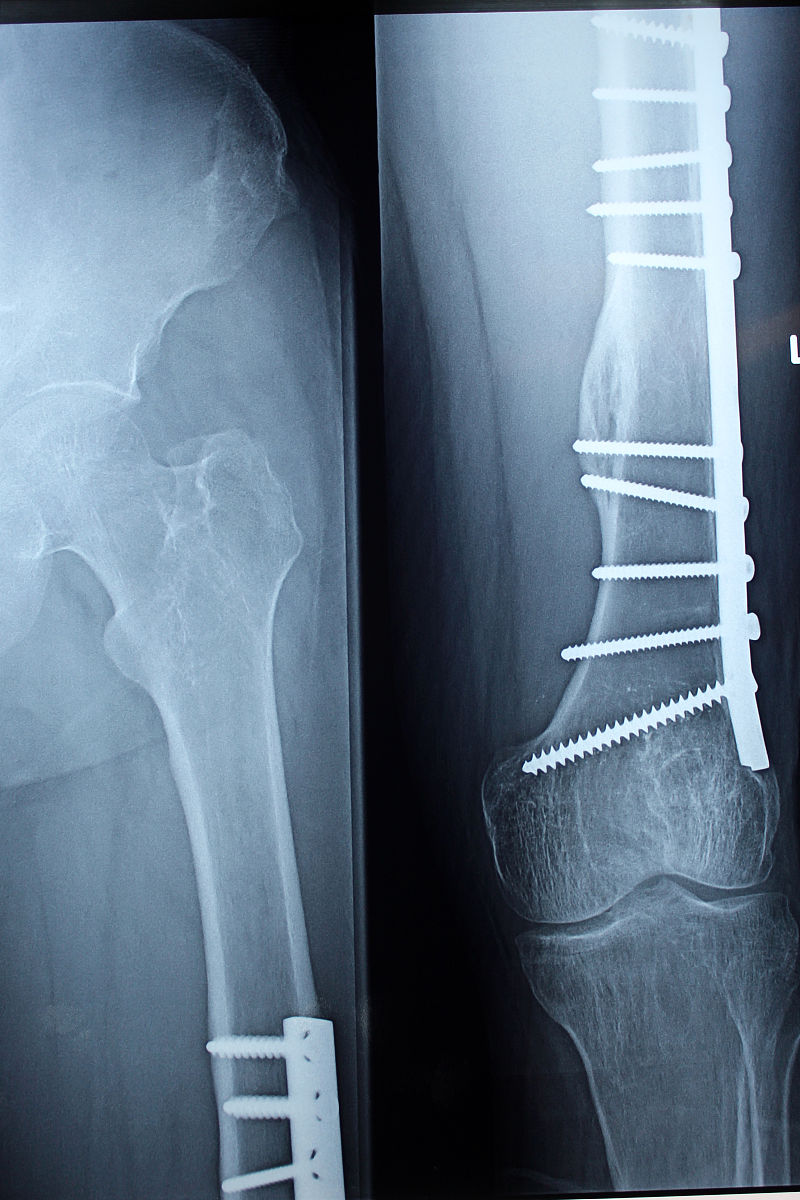

6. 骨折不愈合:术后患者可能出现骨折不愈合的情况。护理人员应鼓励患者进行适当的康复训练,保持骨折部位的稳定,避免过度负重。